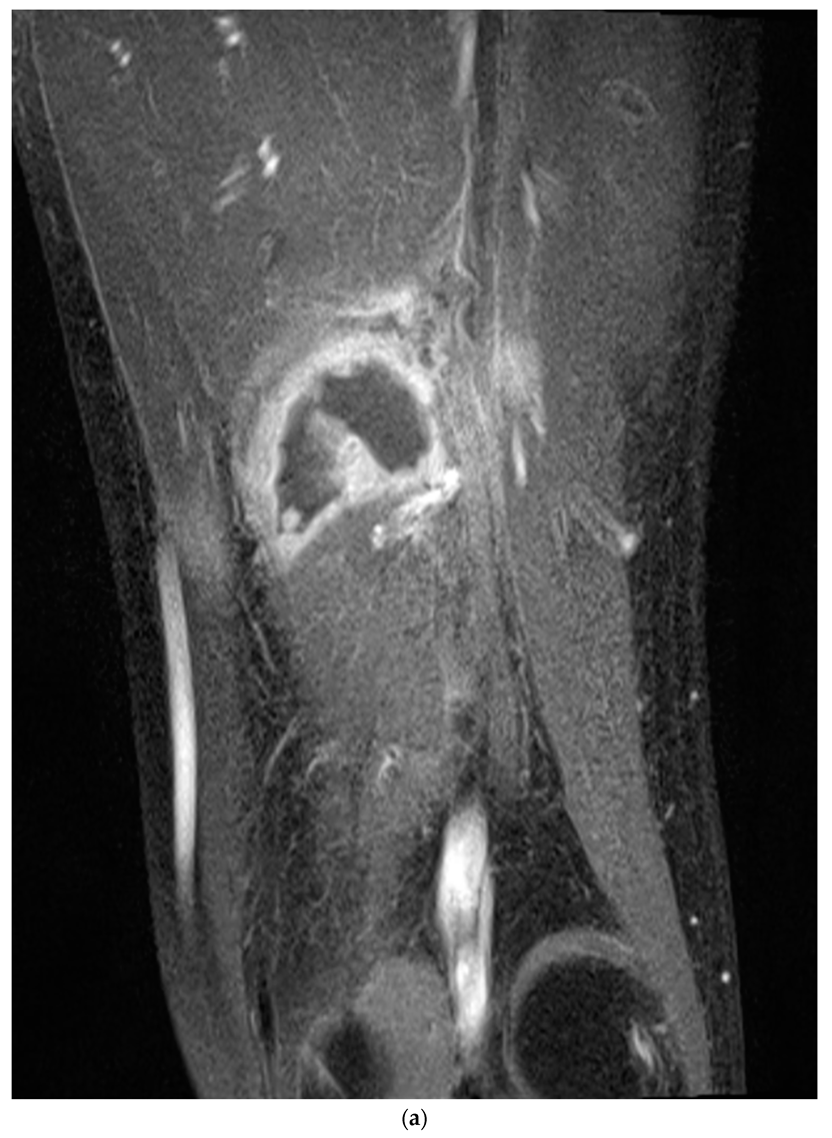

Nerve conduction velocity/electromyography (EMG) was performed and showed a severe sciatic nerve injury at the distal thigh level. Moreover, on computed tomography (CT), ischemic changes were observed in the adductor magnus, biceps femoris long and short head, semimembranosus, and semitendinosus muscles 25 cm below the femoral head, and the length of the lesion was approximately 6 cm (Figure 2a,b). The sciatic nerve in the affected area was observed to be swollen compared to the contralateral side, and the intermuscular fat was accompanied by haziness. Ischemic changes were observed in the posterior thigh muscles on magnetic resonance imaging (MRI), similar to the previous CT scan. In addition, the sciatic nerve was severely swollen compared with the contralateral side, and the T2-weighted signal intensity was increased (Figure 3).

Figure 3. The T1-weighted magnetic resonance (MR) image (a) shows ischemic changes in the thigh posterior muscles, as in the previous CT scan. The sciatic nerve is severely swollen compared to the contralateral side, and the T2-weighted signal intensity (b) is increased (blue arrow). T1-weighted sagittal imaging (c) shows the length of the swollen sciatic nerve (green bracket).